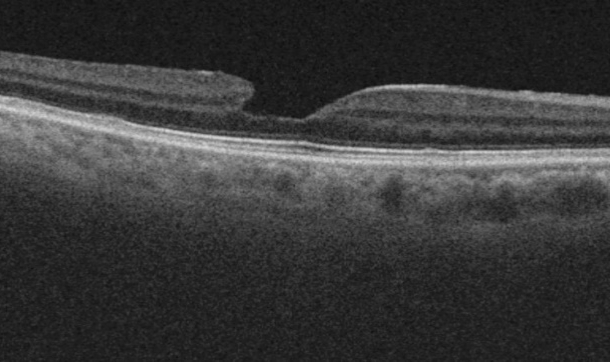

黄斑偽円孔とは?

黄斑前膜の一つに偽円孔というタイプがあります。黄斑の中心を除く黄斑の周りに前膜ができ、前膜の部分が収縮して盛り上がったために、中心が凹んで見えるようになった状態です。あたかも黄斑円孔のように見えるため偽円孔と呼ばれています。